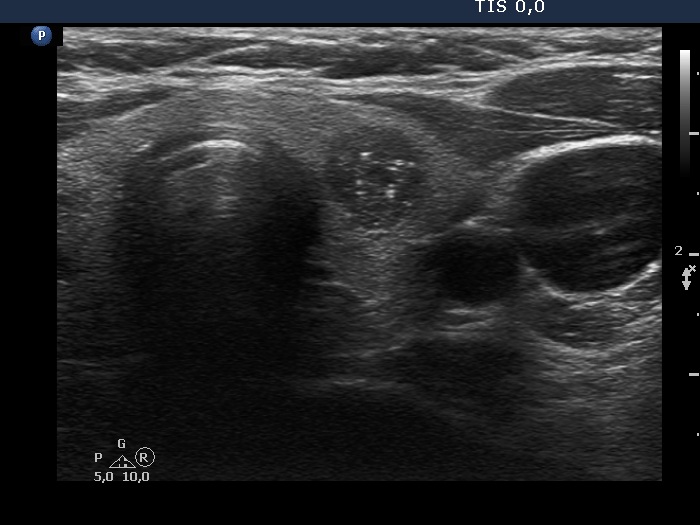

Ultrasonography. The thyroid was echonormal. There was hypoechoic nodule in the left lobe. The nodule had numerous echogenic granules and lines. Video record proved that these are clearly related to ventral cystic areas, therefore these are back wall cystic figures caused by posterior enhancement. The nodule showed taller-than-wide sign.

Comment. This case illustrates why is video clearly superior to still images in analyzing thyroid nodules. Viewing the still image on transverse section (first image in the list), the intranodular echogenic figures seem to be microcalcification. However, video clearly proved the presence of tiny cystic areas ventral to these echogenic figures.